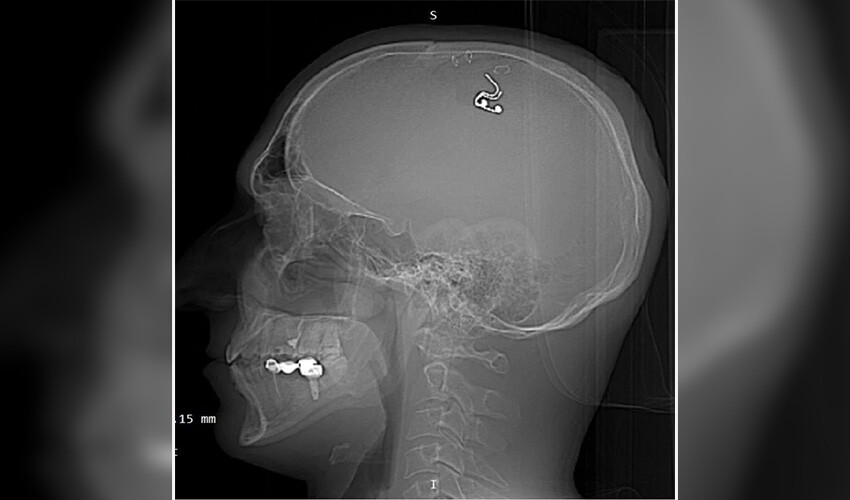

Bir süre sonra çipi kafasına yerleştirmeye karar veren Raduga, matkapla kafatasını deldi. Kan kaybetmeye başladığını fark eden Raduga, en yakın hastaneye başvurdu. Ameliyata alınan Mikhail Raduga’nın kafatasına yerleştirdiği çip çıkarılırken, hayati tehlikeyi atlattığı açıklandı.